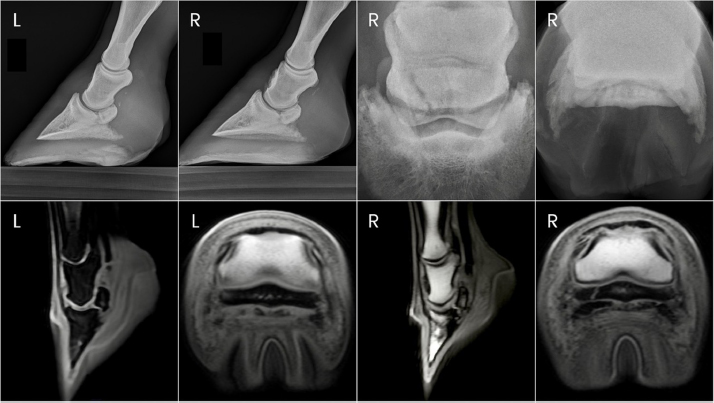

Two years after donation, the gelding progressed to displaying a grade 4/5 right forelimb lameness. This lameness was eliminated with diagnostic anesthesia of the right palmar digital nerves at the level of the proximal interphalangeal joint and replaced by a grade 3/5 left forelimb lameness. The left forelimb lameness was then eliminated with diagnostic anesthesia of the left palmar digital nerves in a similar fashion. PDN was performed as a salvage procedure to maintain pasture soundness. Preoperative radiographs showed severe bilateral navicular bone degeneration with focal mineralization of the DDF tendon bilaterally (Fig. 2).

Fig. 2. Preoperative radiographs of the digits of horse 2.

Horse 1 remained pasture sound until day 84 post-PDN when he was presented for an abnormal gait with both toes displaying a mild dorsal elevation off the ground when weight bearing. Radiographs of the digits revealed parasagittal fractures of both forelimb navicular bones with hyperextension of both DIPJs (Fig. 3). Severe fiber pattern disruption of the DDF tendon was noted on ultrasound of both forelimb palmar pastern regions suggestive of severe DDF tendinopathy or rupture. Humane euthanasia was elected due to the severity of the pathology and poor prognosis. Postmortem magnetic resonance imaging (MRI) was performed on the forelimbs, which identified marked navicular bone degeneration with obliquely oriented, complete fractures of the lateral quarter of the navicular bone bilaterally, complete rupture of the DDF tendon extending from the distal aspect of the first phalanx to the navicular bone in the right forelimb, and nearly complete rupture of the DDF tendon in the left forelimb (Fig. 3). Additional findings of note in both forelimbs were hyperextension of the DIPJ, significant navicular bursitis with probable bursal adhesions, and desmitis of the impar, collateral sesamoidean, and distal digital annular ligaments.

Fig. 3. Antemortem radiographs and postmortem MRI images of horse one showing bilateral navicular bone fractures, DIPJ hyperextension, and DDF tendon compromise.